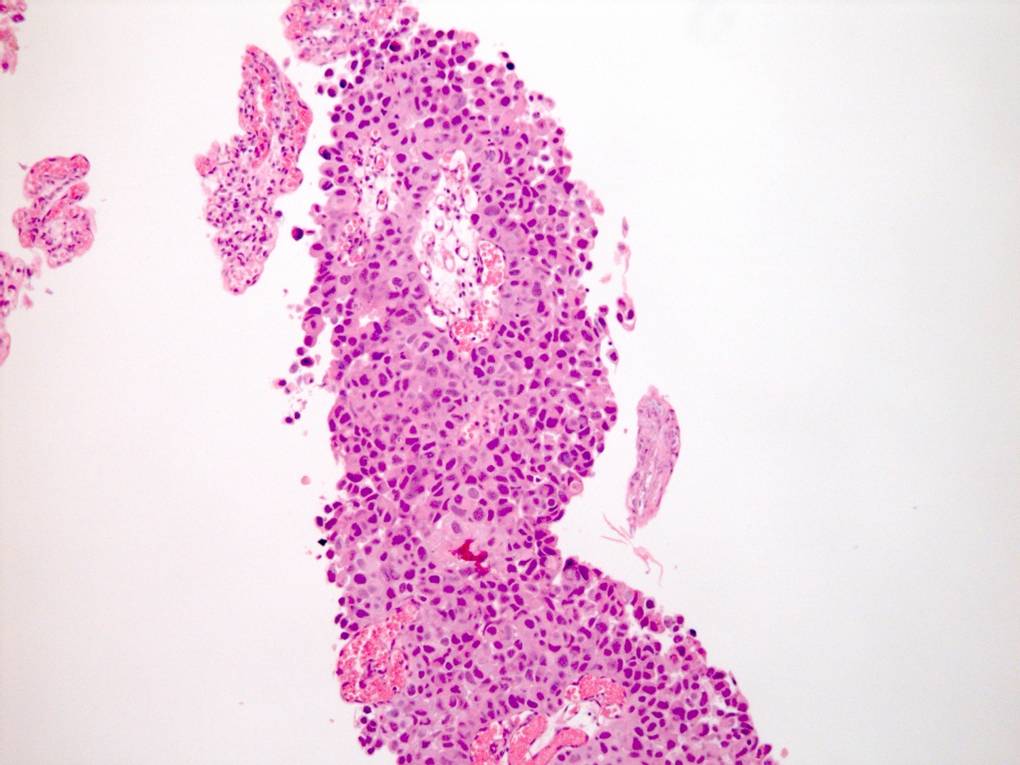

Consensus grade: High-grade papillary urothelial carcinoma (HG-PUC)

Case description (by case creator):

61 year old male. History of haematuria. Diagnosis = high grade papillary urothelial carcinoma with lamina propria invasion.